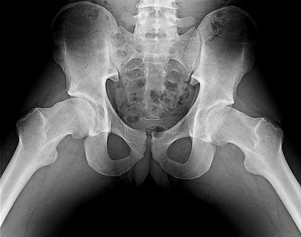

Figure 19 is an anteroposterior pelvis radiograph of a 60-year-old woman who has a 4-month history of right hip pain. She has a

medical history of lupus and has used

21

prednisone in the past, but not currently.

Her pain is persistent despite use of over-the-counter pain medications and activity modifications. What is the most appropriate treatment at this point?

This scenario describes osteonecrosis of the hip, likely attributable to chronic corticosteroid use. Her radiographs show bilateral hip involvement with whole-head involvement and collapse of the femoral head. Observation, protected weight bearing, and bisphosphonates have been advocated during the precollapse stage, but, considering the advanced

involvement of the femoral heads, these treatments are not indicated. Hip arthroplasty is the most reliable treatment option at this point to resolve her symptoms. Total hip resurfacing is not indicated for multiple reasons, including poor bone stock from corticosteroid use and her age. Large-head involvement and concerns about metal-on-metal articulation in someone with potential for renal impairment (such as a patient with lupus) also are contraindications to total hip resurfacing. Total hip arthroplasty will offer the best chance for success.